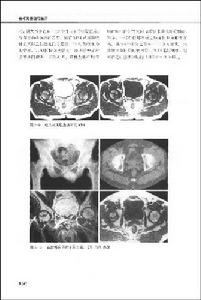

第二節 股骨頭壞死